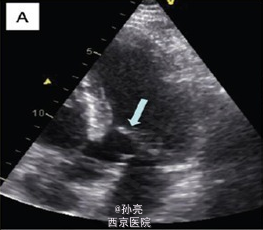

48 岁男性患者,4 年前因梗阻型肥厚性心肌病曾于我院医疗中心行室间隔无水酒精消融术。尽管术后使用β受体阻滞剂、异搏定和丙吡胺,患者仍有劳力性呼吸困难症状出现。 结合既往心脏 CT 片对照,未发现有意义的冠状动脉病变。室间隔壁为 12mm 厚。更进一步,我们观察到收缩期时二尖瓣有一个不同寻常的组织突出于左室流出道(图 1B)。 这种机械方面的梗阻我们再次用经胸壁超声得以证实,当多余的组织靠近室间隔时,该组织与最大收缩期左室流出道的压力阶差为 80mmHg(图 1B)。 心脏 MRI 再次确认出现的二尖瓣附件组织阻塞左室流出道,加速了收缩期的血液流动(图 1C)